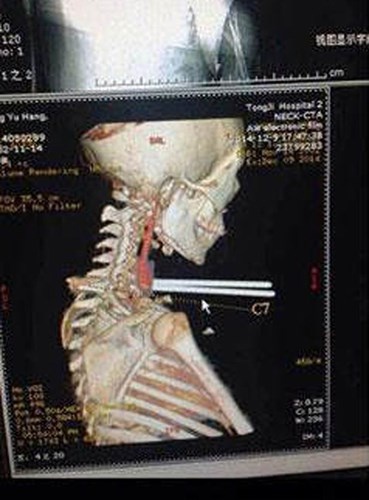

| Anh Andrew Linn 28 tuổi tại Las Vegas Andrew, đã gặp phải vụ tai nạn có một không hai khi đang lái xe trong tình trạng buồn ngủ. Linn đã lao xe ra khỏi hướng đang lưu thông trước khi đâm phải hàng rào bằng kim loại. Các nhân viên cứu hộ đã phải cắt ống kim loại để đưa tài xế ra khỏi xe và chuyển khẩn cấp tới bệnh viện. Đội ngũ y tế tại đã có thể loại bỏ ống kim loại mà không gây hại đến động mạch cảnh và tĩnh mạch cổ. |